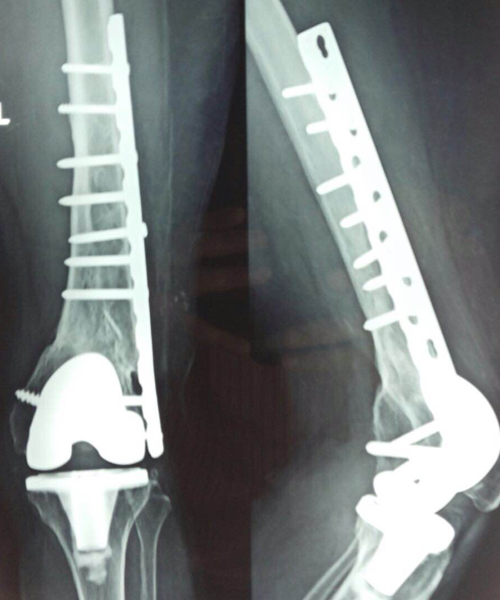

Case:14 Periprosthetic Fracture

60 years old patient with total knee replacement on left knee presented with open grade 1 injury. Debridement & slab given on emergency bases. Fixation with plate & screws done. Union was seen after 6 months.

Pre-Op AP

Pre-Op Lat.

Immdiate Post-op

1 and half months Post-op

2 and half months Post-op

3 and half months Post-op

4 and half months Lateral

6 Years Follow-Up